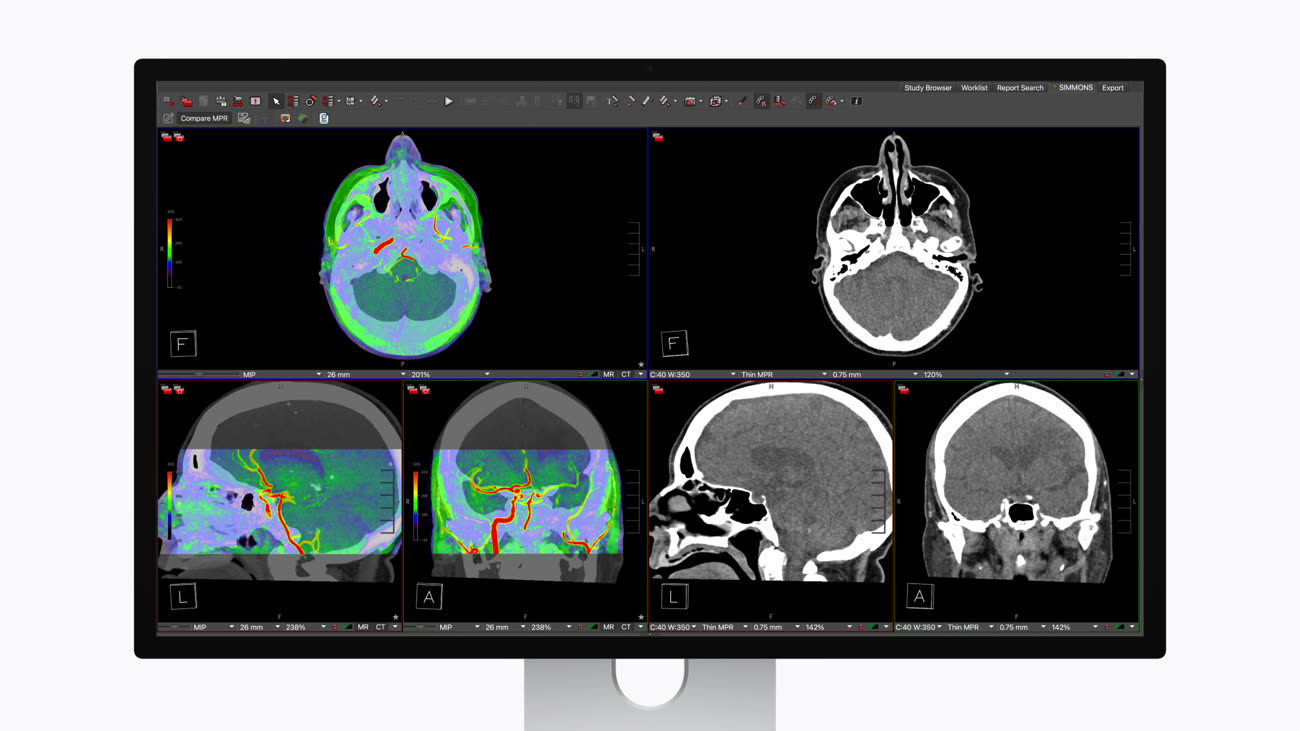

La grande nouveauté réside dans la prise en charge des préréglages d’imagerie médicale DICOM, le standard international pour les images médicales. Grâce à un nouvel outil baptisé Medical Imaging Calibrator, le Studio Display XDR peut désormais être utilisé pour le diagnostic radiologique.

L’idée d’Apple est simple : permettre aux radiologues de consulter et d’analyser des clichés directement sur leur écran de travail quotidien, sans avoir à basculer sur un moniteur spécifique à usage unique. Pour faciliter la transition, un commutateur logiciel permet de passer instantanément du mode de visualisation standard au mode radiologique.

Pour convaincre les praticiens, Apple s'appuie sur une débauche de technologies qui prend tout son sens dans l'imagerie de précision. L'écran embarque un rétroéclairage mini-LED doté de 2 304 zones de gradation locale, offrant une luminosité de pointe HDR à 2 000 nits et un contraste de 1 000 000:1 pour ne rater aucun détail. Avec l'apport du ProMotion 120 Hz et une précision colorimétrique de pointe, le Studio Display XDR s'affirme comme un outil de diagnostic redoutable, capable de faire de l'ombre aux acteurs historiques du secteur.